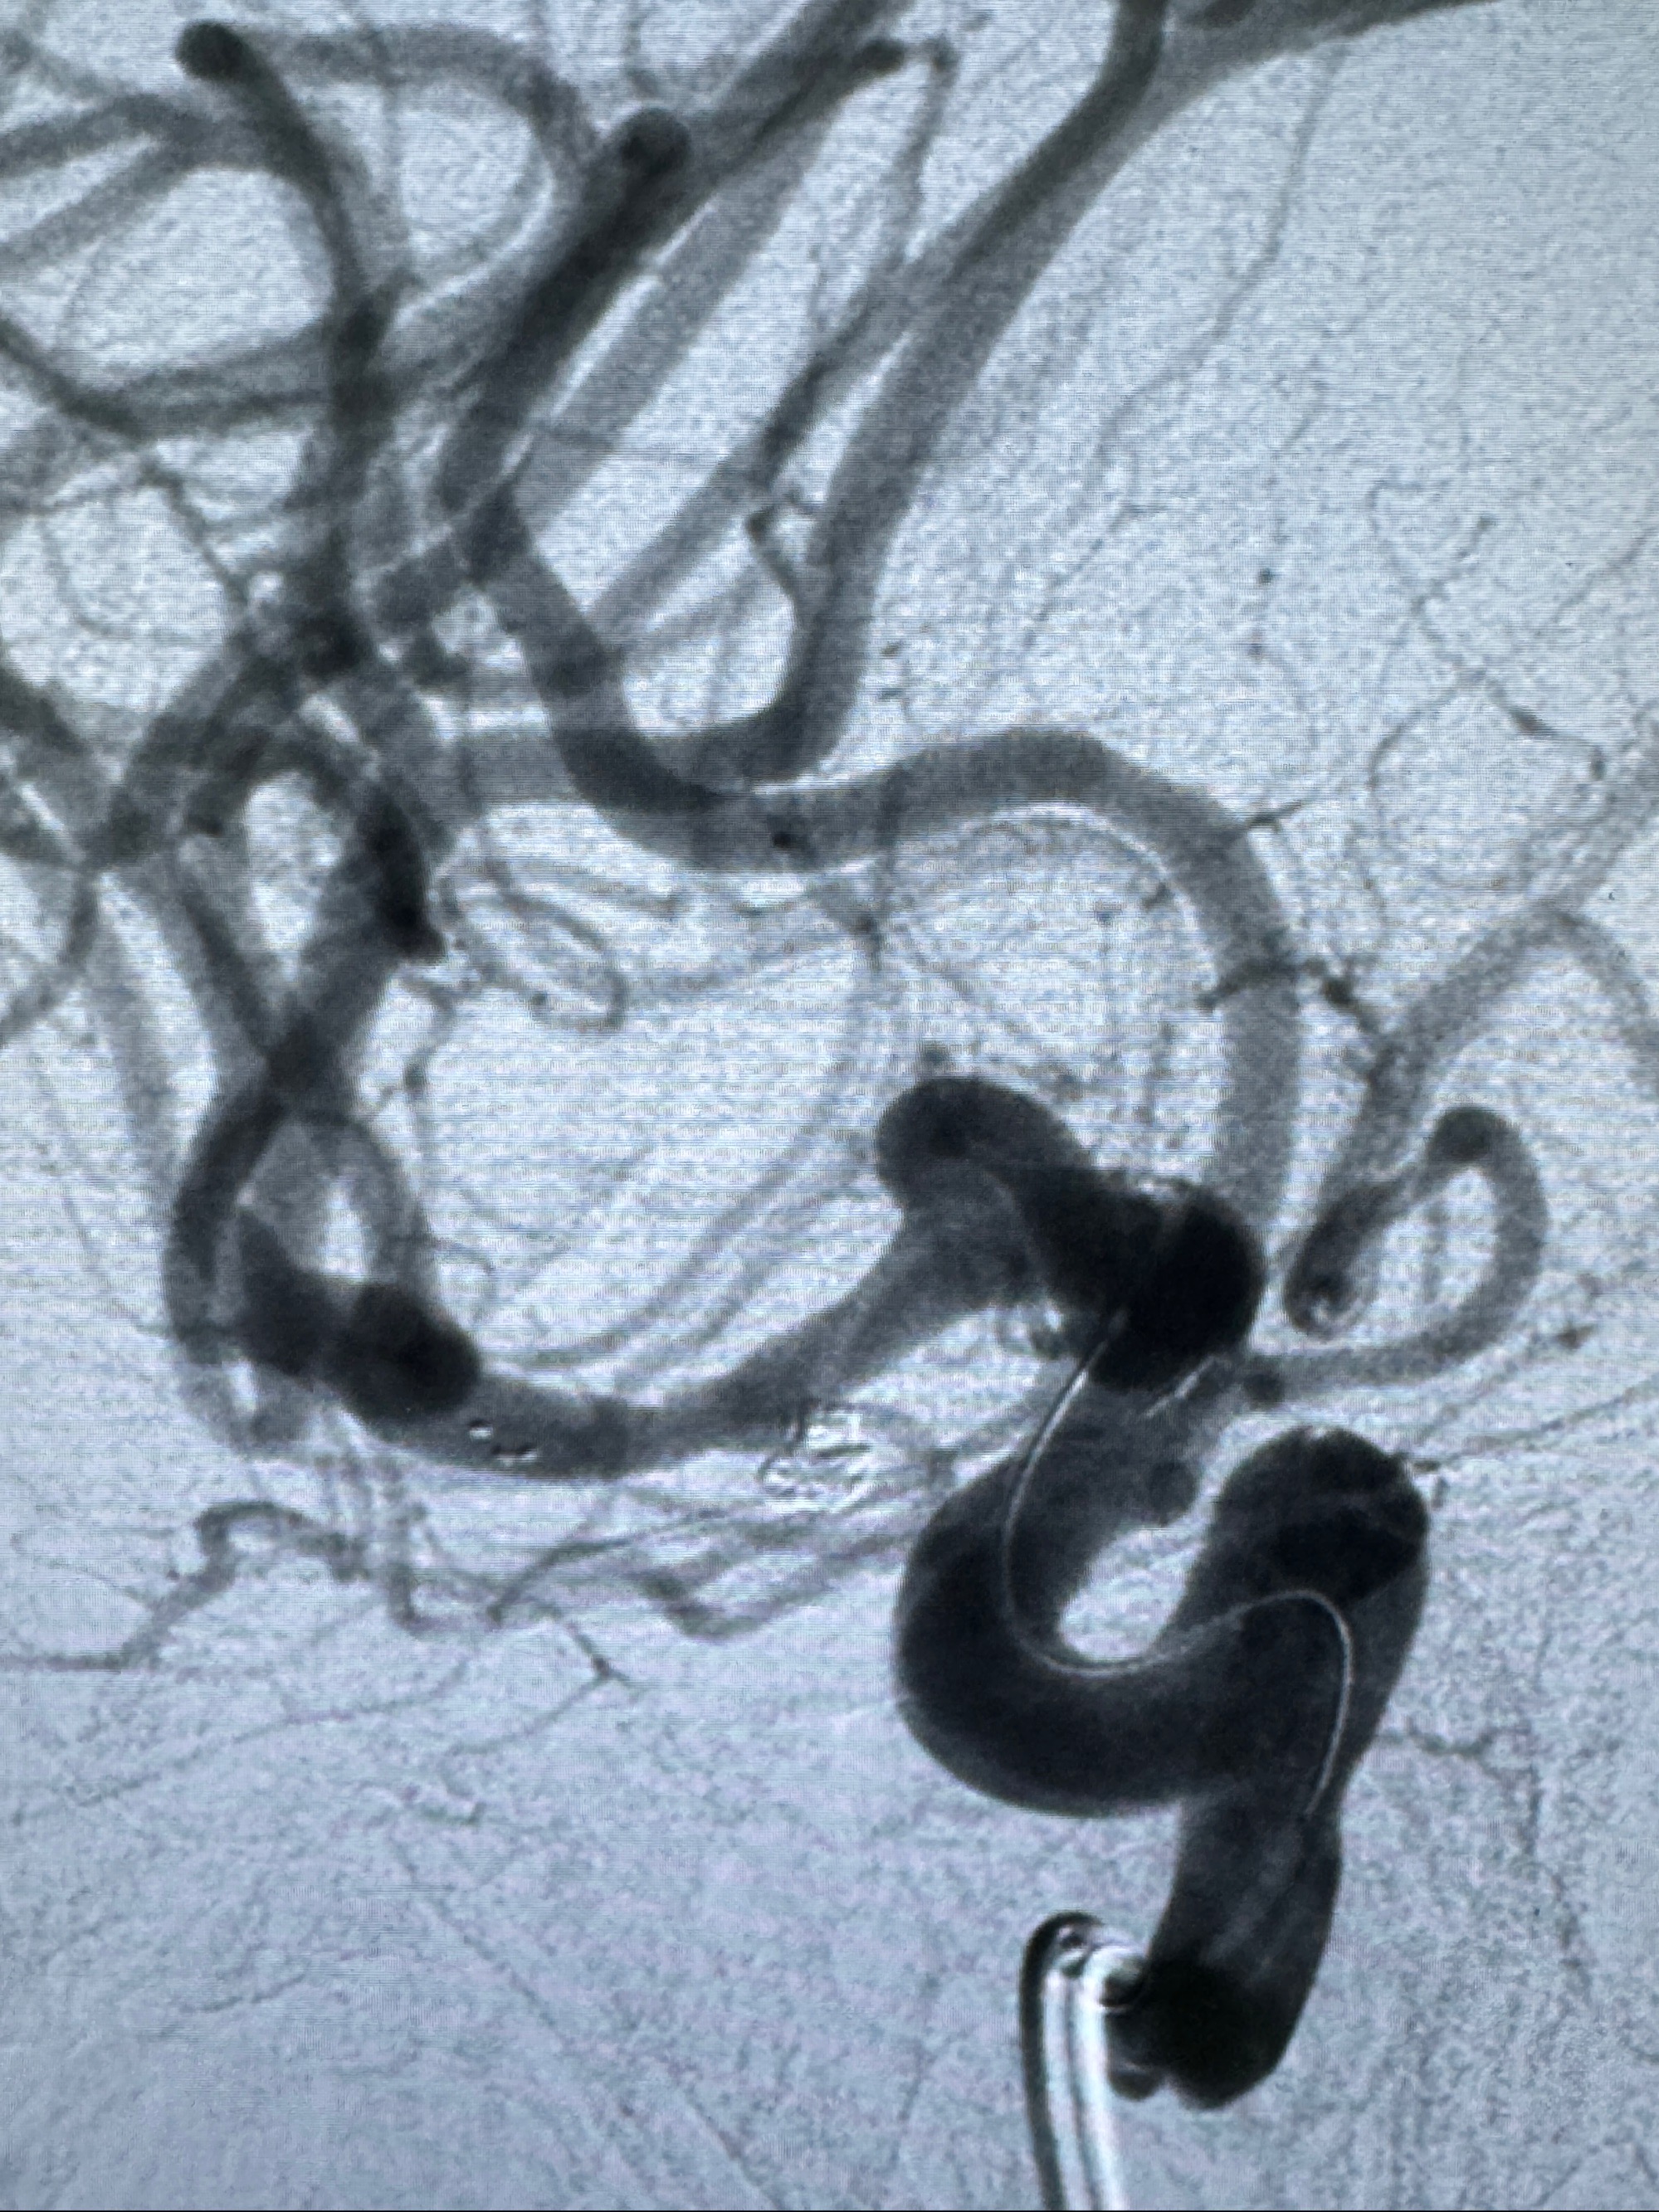

2023-11-24DSA:右侧大脑中动脉下干起始部动脉瘤,约2.3*2.5mm,形态规则

2023-12-04全麻下行支架辅助治疗

S-AB4-20mm